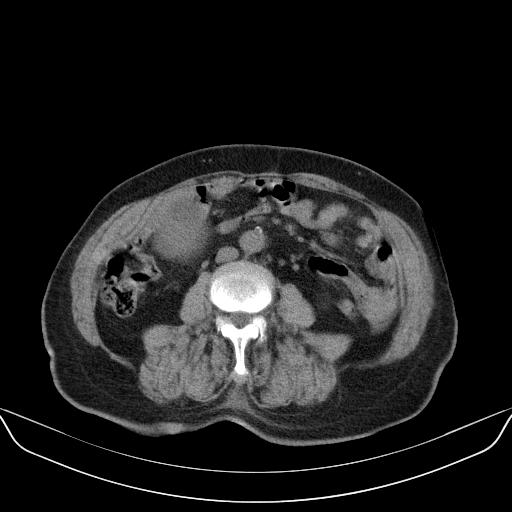

以下是引用yuhongjun在2010-3-12 6:32:00的发言:[br]回肠末端间质瘤,不除外阑尾粘液囊腺瘤,臀部注射性肉芽肿钙化. [br] [br]